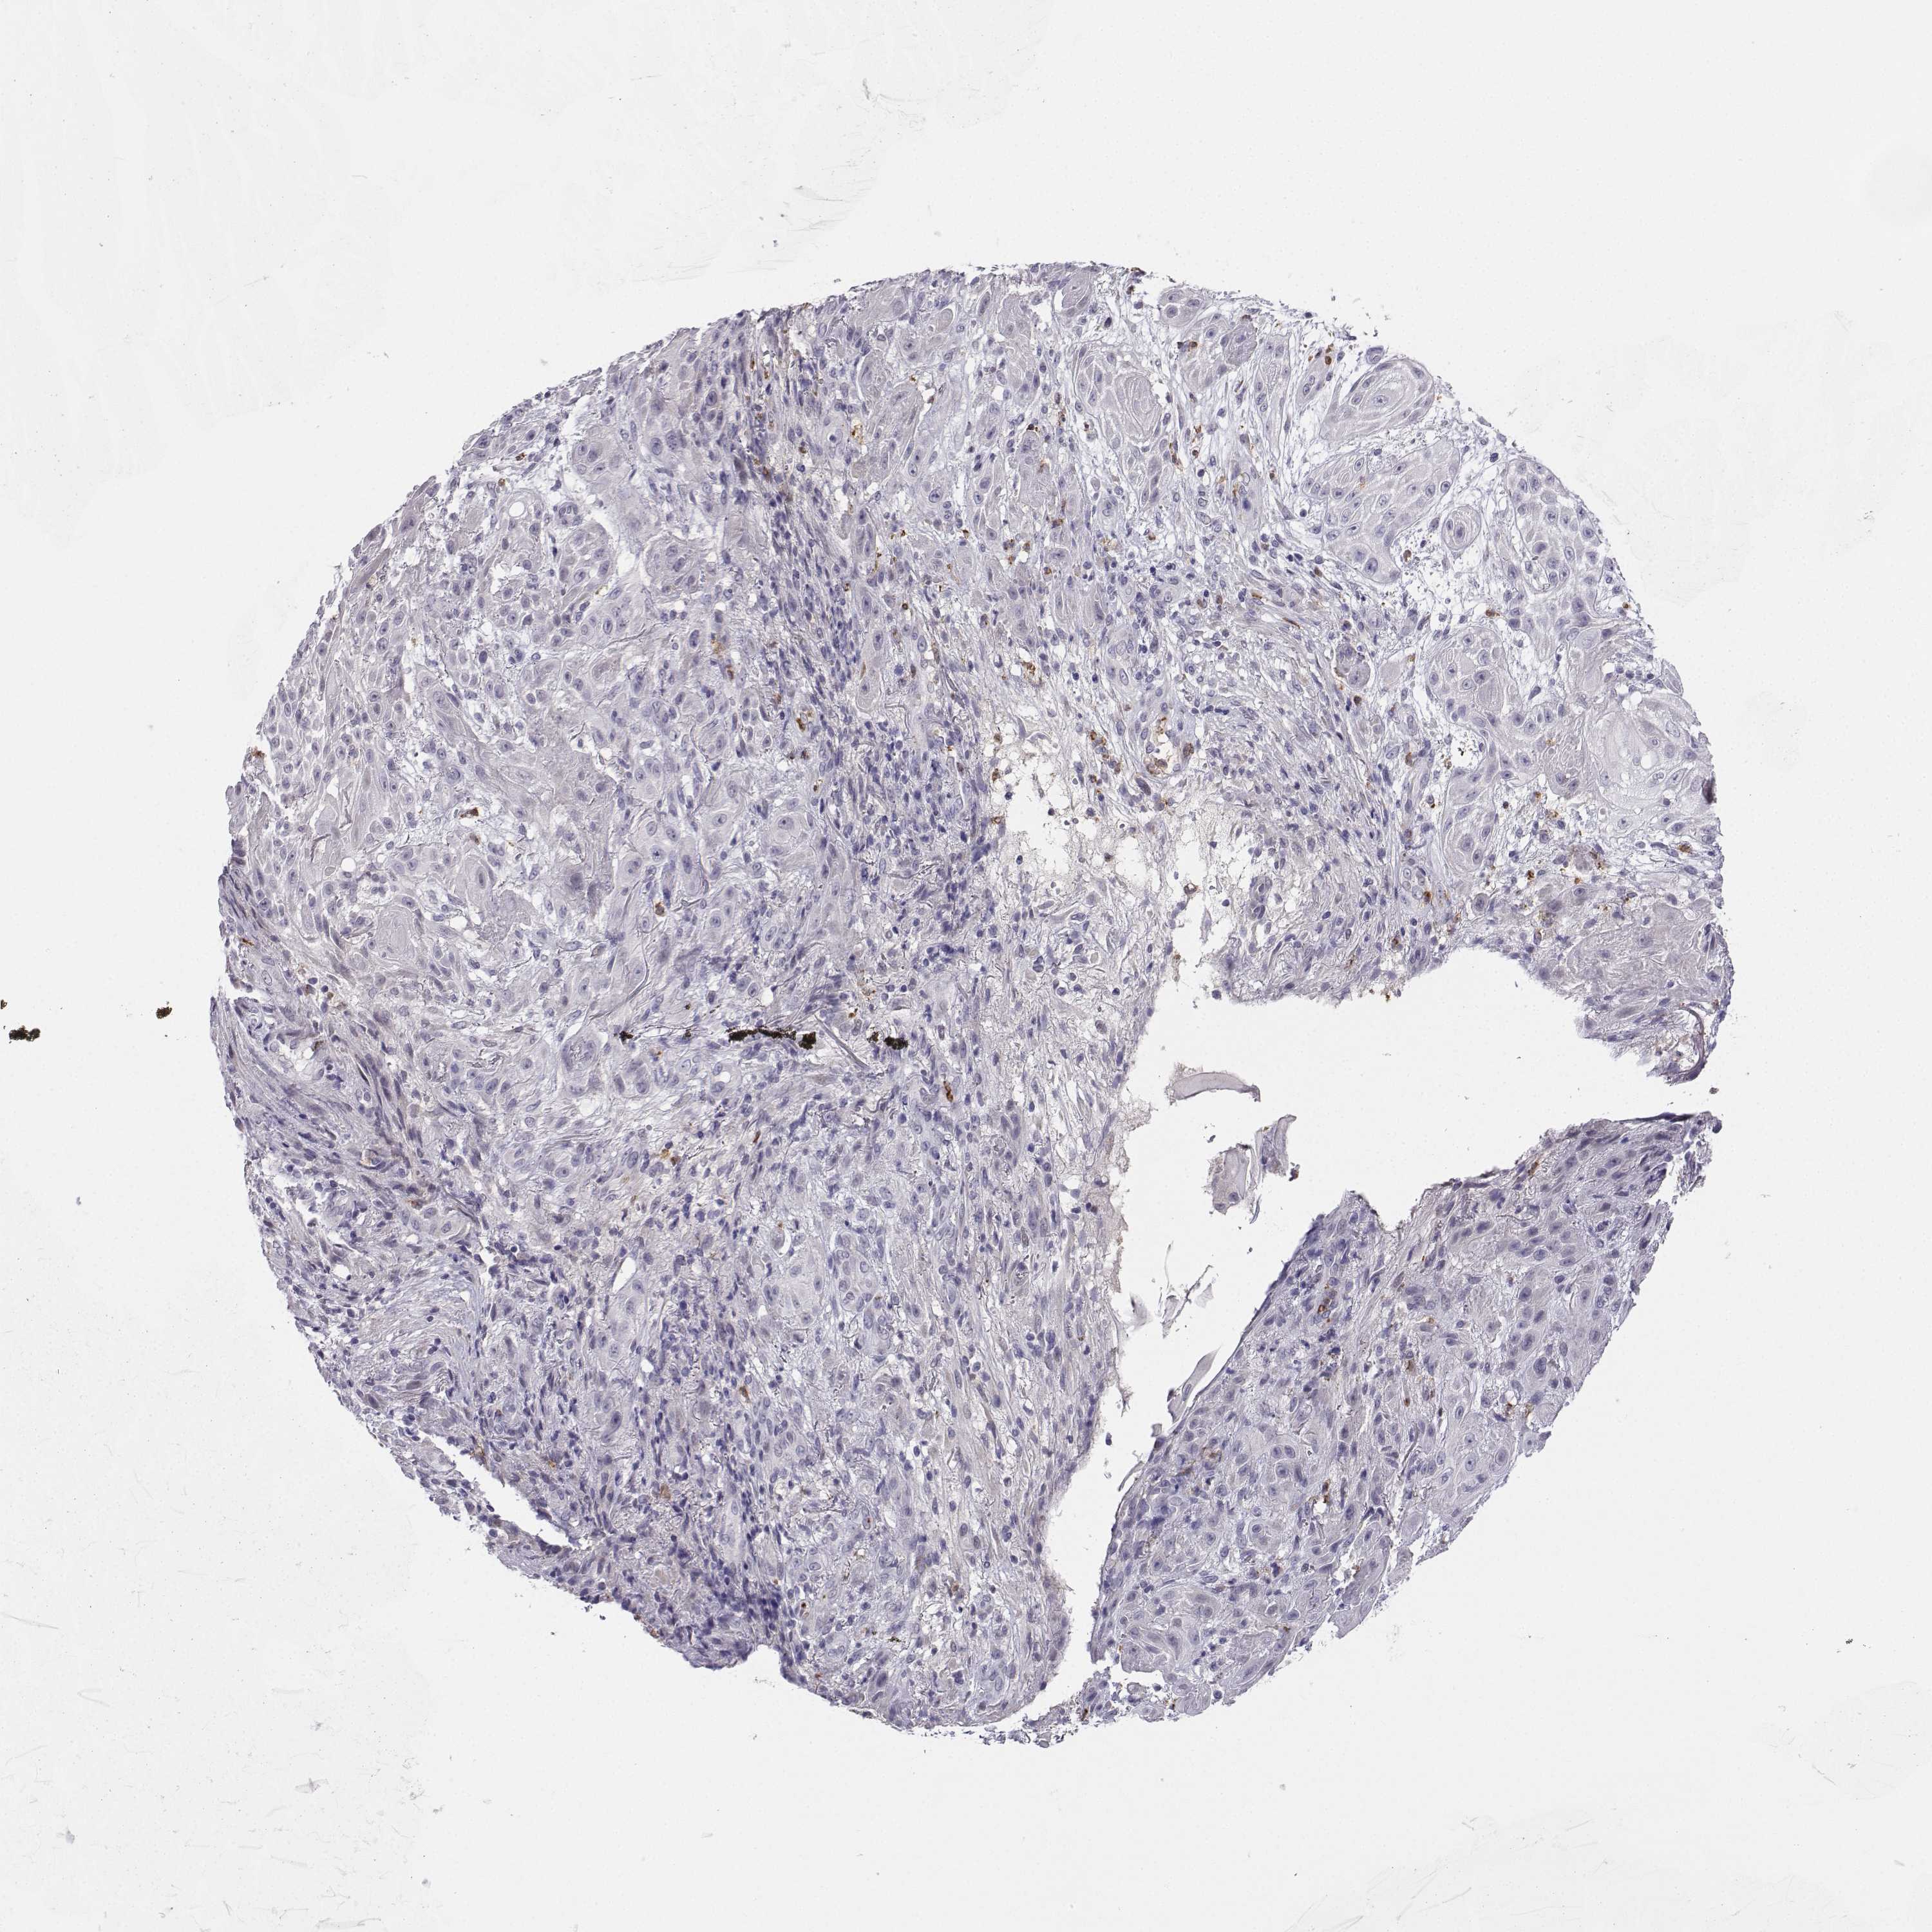

SKIN CANCER - Protein expressioni

A mouse-over function shows sample information and annotation data. Click on an image to view it in a full screen mode. Samples can be filtered based on level of antibody staining by selecting one or several of the following categories: high, medium, low and not detected. The assay and annotation is described here.

Antibody stainingi

Antibody staining in the annotated cell types in the current human tissue is reported as not detected, low, medium, or high, based on conventional immunohistochemistry profiling in selected tissues. This score is based on the combination of the staining intensity and fraction of stained cells.

Each image is clickable and will lead to virtual microscopy that enables deeper exploration of all samples and also displays staining intensity scores, fraction scores and subcellular localization as well as patient and tissue information for each sample.

Antibody HPA042283

Basal cell carcinoma

Squamous cell carcinoma, NOS